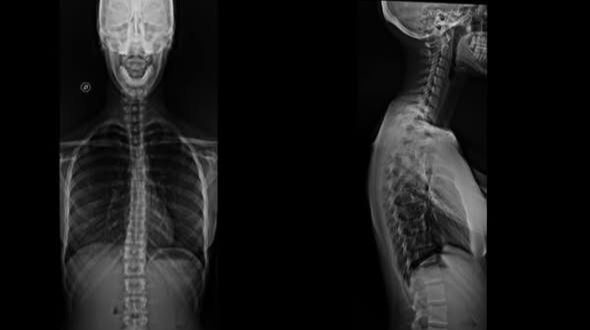

Espino-gramas: unión de imágenes para visualizar la columna completa (desde el cuello hasta la pelvis) en una sola placa, fundamental para el tratamiento de la escoliosis.